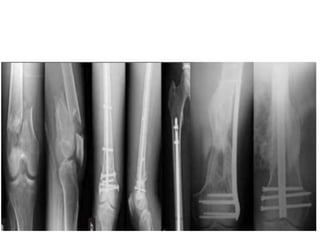

Operative

External fixation temporizing measure until soft

tissues permit internal fixation, or until patient is stable

avoid pin placement in area of planned plate placement if

possible

ORIF indications : 1- displaced fracture 2- intra-articular

fracture 3- nonunion - goals : 1- need anatomic reduction of joint

2- stable fixation of articular component to shaft to permit early

motion 3- preserve vascularity

Retrograde IM Nail

Treatment Non - Operative Skeletaltraction Casting and bracing for 6 weeks : indications (rare) >> - non displaced fractures - non ambulatory patient - patient with significant comorbidities

• 13.

Operative External fixation temporizingmeasure until soft tissues permit internal fixation, or until patient is stable avoid pin placement in area of planned plate placement if possible ORIF indications : 1- displaced fracture 2- intra-articular fracture 3- nonunion - goals : 1- need anatomic reduction of joint 2- stable fixation of articular component to shaft to permit early motion 3- preserve vascularity Retrograde IM Nail